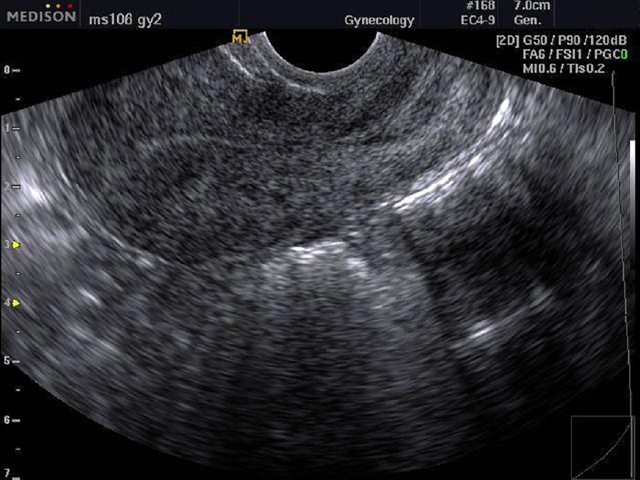

Трансвагинальная УЗИ-диагностика

Размеры матки в норме у женщин, расположение органа, толщину эндометрия и расположение яичников позволяет наиболее точно выявить трансвагинальная диагностика. Для этого датчик, который представляет собой пластиковый стержень 12 см в длину, вводится на небольшую глубину.

Процесс не доставляет неудобств, так как используется специальный гель, а диаметр устройства составляет всего 3 см. Из-за небольшой толщины стенок влагалища удается обнаружить любые, даже незначительные изменения. Благодаря этому, удается установить точный диагноз и подобрать своевременное лечение.

Узнать, в норме ли размеры матки у женщин можно благодаря трансвагинальному УЗИ.

При этом исследовании доступ во влагалище женщины вводится специальный датчик, на который надет одноразовый презерватив для эндоскопических манипуляций.

Трансвагинальное УЗИ матки — высокоинформативная процедура, так как визуализация, в этом случае, лучше.